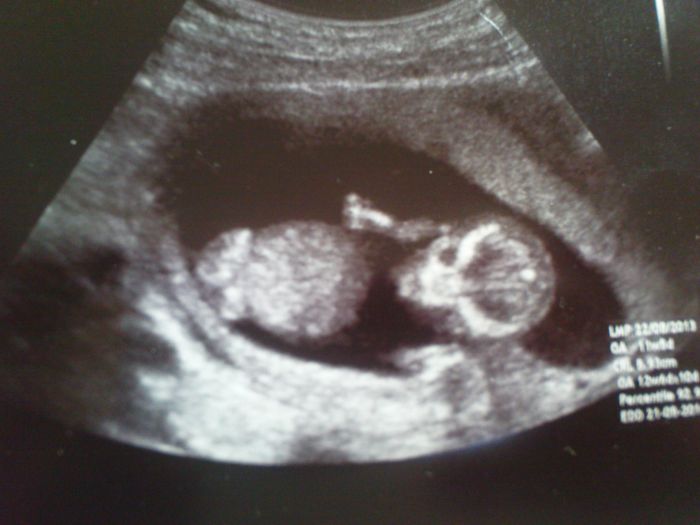

Ahoj holky, dneska začínám 14.týden, tak jsem doufala, že mi už nebude zle...Ale ranní nevolnosti pokračují, takže na náladě mi to nepřidá. Ach jo. Výsledky kombinovaného screeningu dopadly dobře, mimi vypadá jak ufon. Přikládám foto.

[393329] No krásnej ufounek.

Terííí...ten ufounek je moc krásnej, je to výstavní kostřička